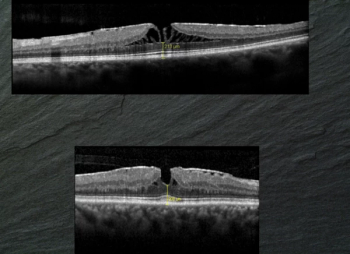

Lamellar holes usually don’t require treatment, but it is important to recognize the eyes that may benefit from vitrectomy.